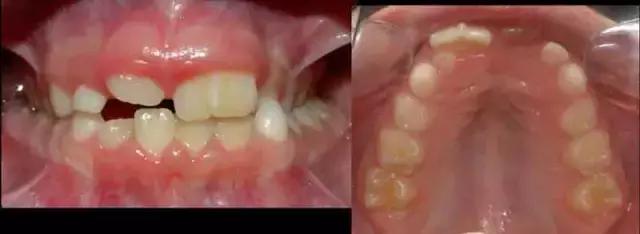

孩子刚长出两颗上门牙的时候,家长发现他的左边牙齿(图中右侧)是正常的,但右边的牙齿看着就像两颗牙齿连在了一起。

家长感到困惑了:这是什么?到底是一颗牙齿还是两颗牙齿呢?其实,真的不好判断。我们需要等到孩子旁边的乳牙也长出来了,才好“下定论”。

一年以后,孩子的其他上前牙也相继地萌出。看图数数,如果把孩子连着一起的牙齿当作是一颗牙的话,孩子正好有4颗上前牙,数目上符合牙齿生长规律。这类型的双牙畸形属于双生牙。